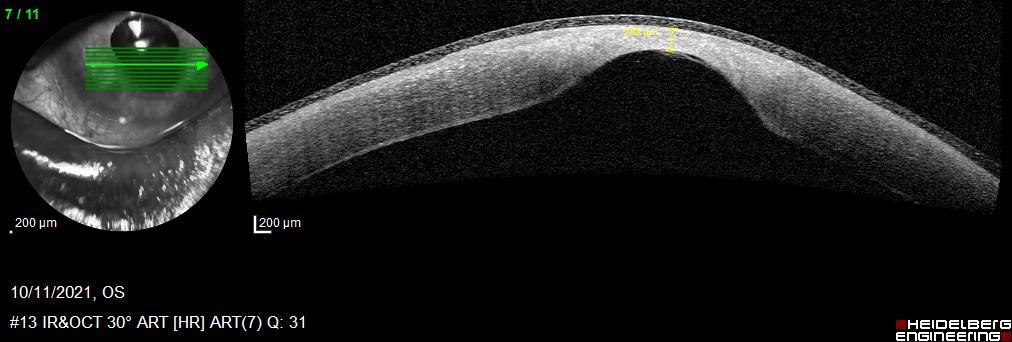

Initially, we filled the anterior chamber of the right eye with some air and patched the corneal defect with fibrin glue sealant (Tissucol ®). Then, we put a contact lens and added some topical antibiotics, and cycloplegic and artificial eye drops. Two days later, in the left eye, the corneal tissue was thinner and on the verge of perforation [figure 3]. Due to the urgency, surgical intervention was performed with an amniotic membrane graft. We used caruncular anesthesia. Two days later, there was no amniotic membrane graft. Rather, stromal thinning and descemetocele were found. We started to introduce amniotic membrane eye drops four times a day to our treatment for two months. We were not hopeful that this would work and the possibility of performing an evisceration was even raised. We followed up the evolution of the corneal thickness development with anterior segment optical coherence tomography [figure 4]. In two months the thickness went from 122 μm to 550 μm [figure 5].